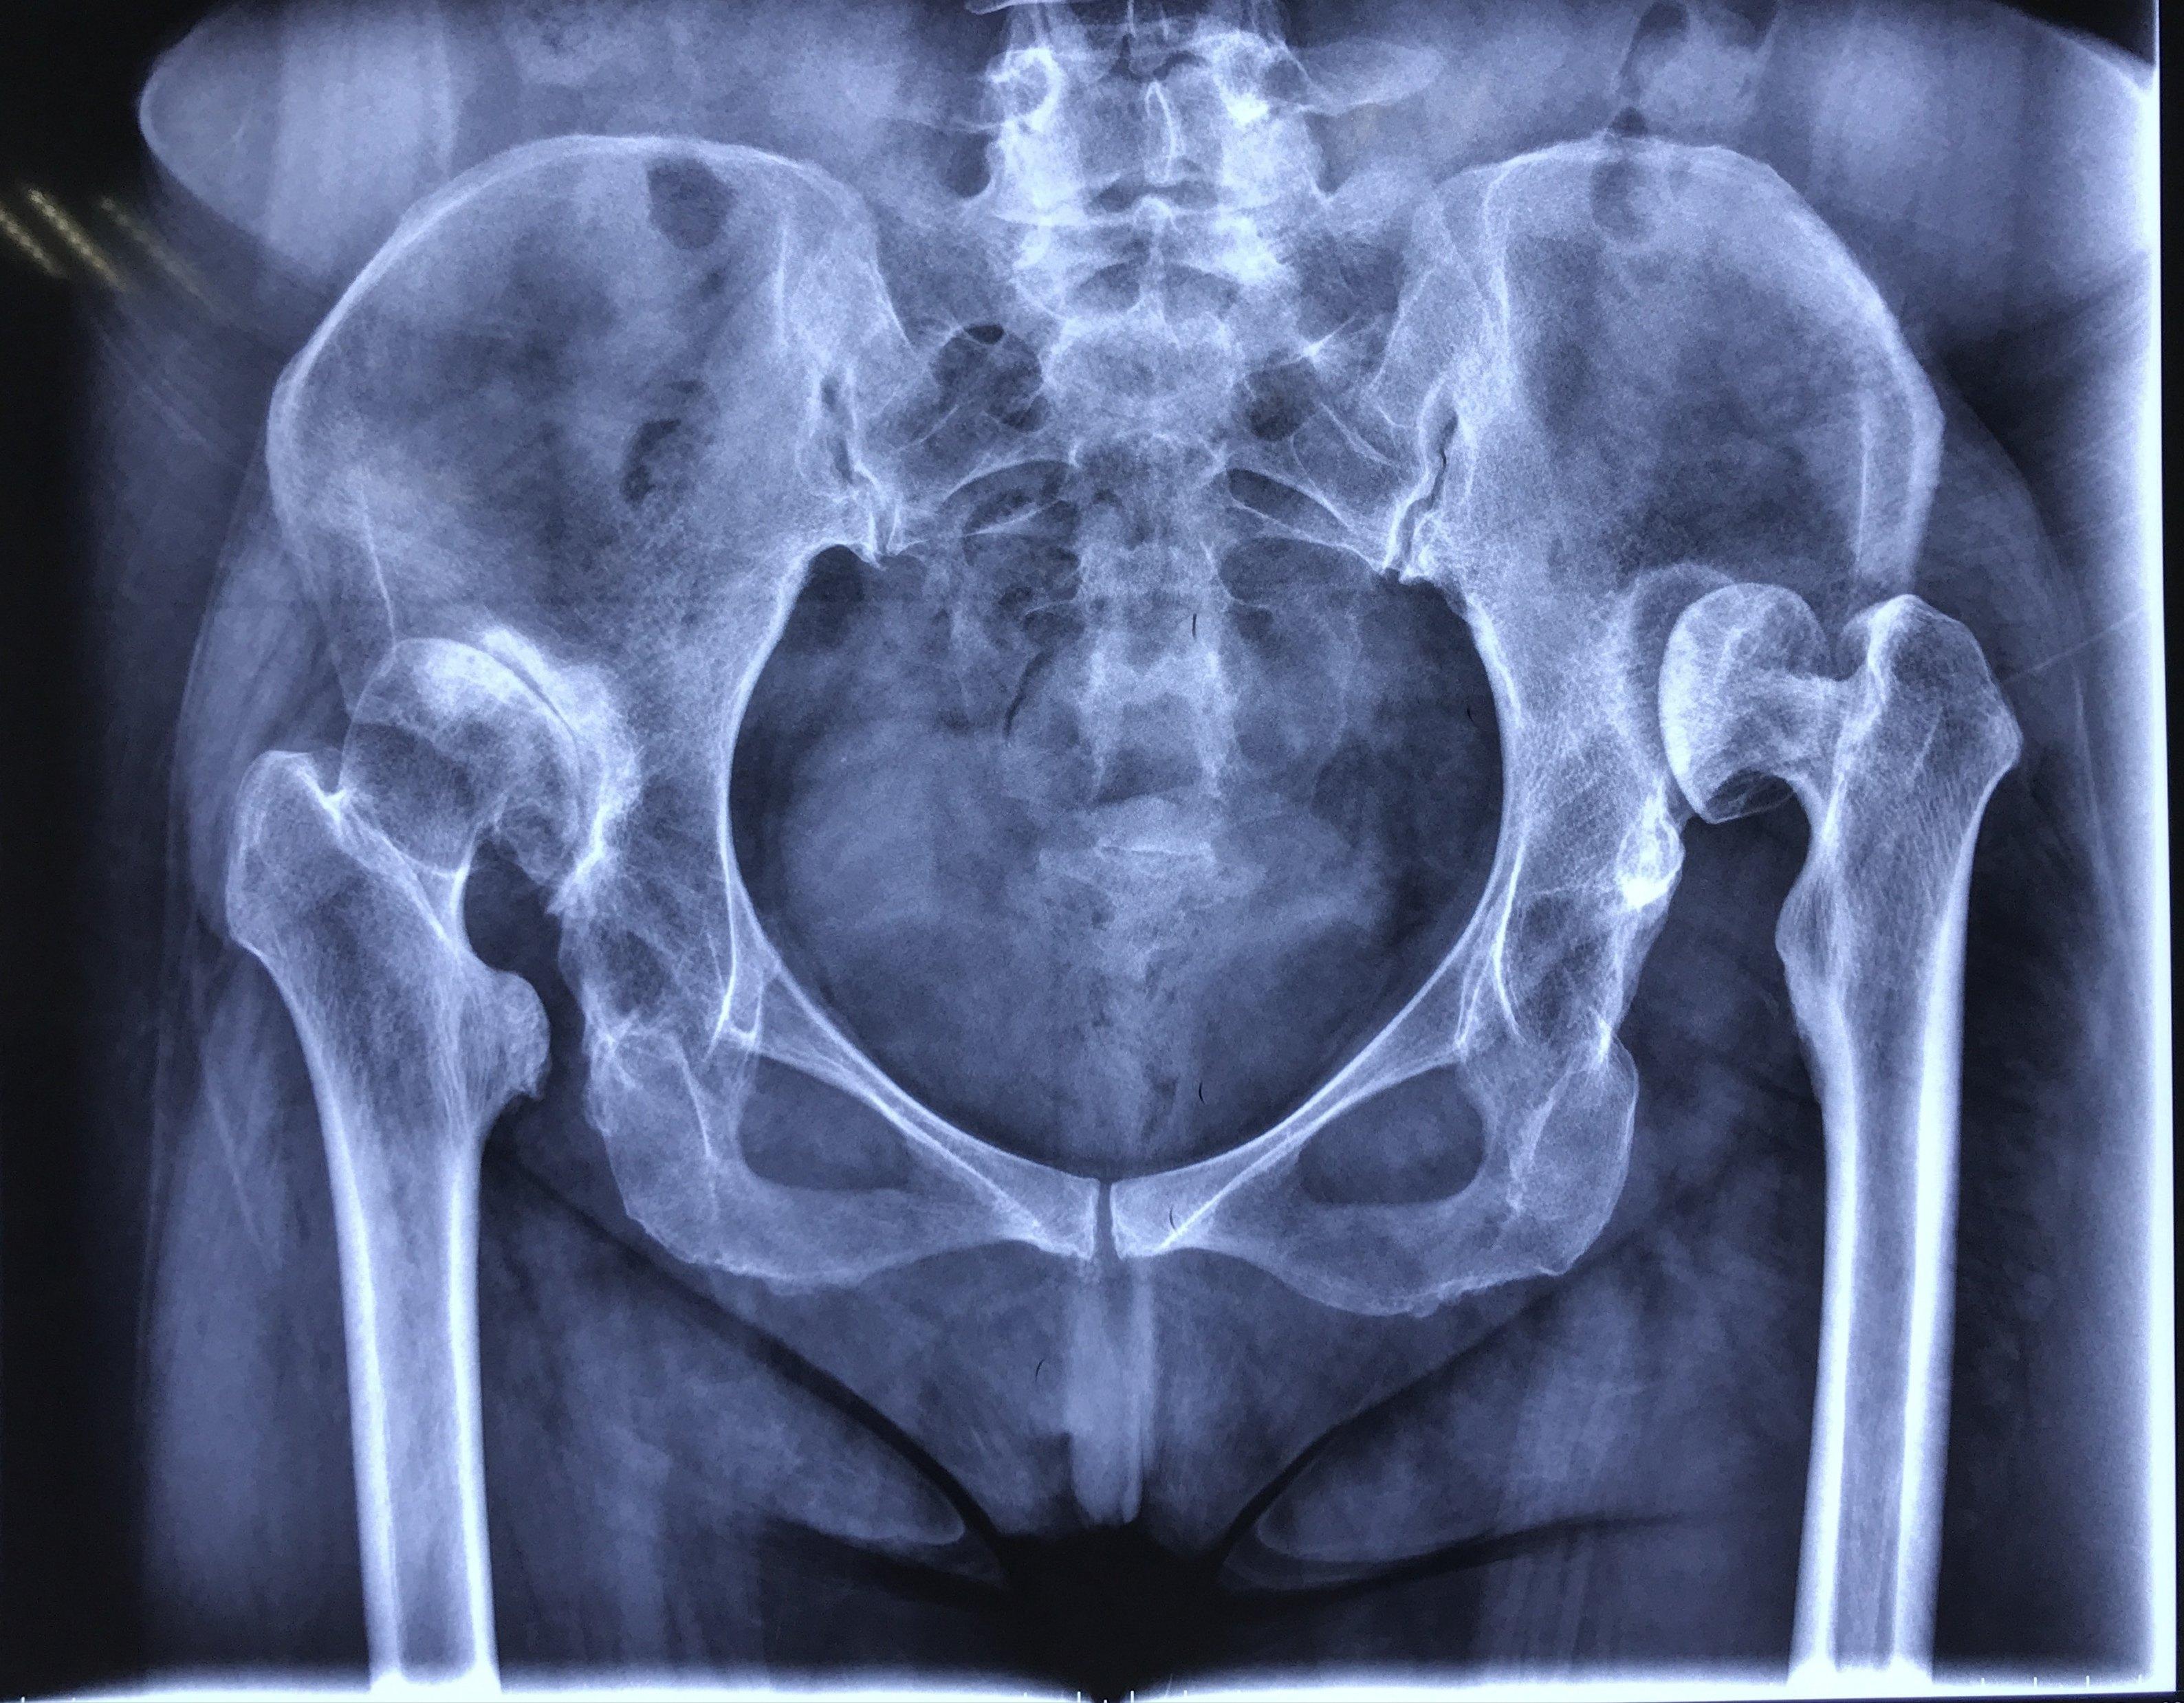

右髋关节脱位后畸形发育,现准备手术治疗,大家有什么好的建议没有?

5岁,左髋关节半脱位,双侧髋臼发育不良,3年间断复查,现医生说需手术